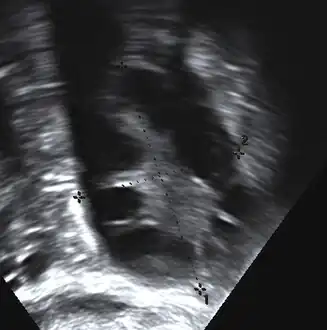

The syndrome acquired its most widely used name due to the common sign on ultrasound examination of multiple (poly) ovarian cysts. These "cysts" are in fact immature ovarian follicles. The follicles have developed from primordial follicles, but this development has stopped ("arrested") at an early stage, due to the disturbed ovarian function. The follicles may be oriented along the ovarian periphery, appearing as a 'string of pearls' on ultrasound examination.[89]

Transvaginal ultrasound scan of polycystic ovary

Polycystic ovary as seen on sonography

- Gynecologic ultrasonography, specifically looking for small ovarian follicles. These are believed to be the result of disturbed ovarian function with failed ovulation, reflected by the infrequent or absent menstruation that is typical of the condition. In a normal menstrual cycle, one egg is released from a dominant follicle – in essence, a cyst that bursts to release the egg. After ovulation, the follicle remnant is transformed into a progesterone-producing corpus luteum, which shrinks and disappears after approximately 12–14 days. In PCOS, there is a so-called "follicular arrest"; i.e., several follicles develop to a size of 5–7 mm, but not further. No single follicle reaches the preovulatory size (16 mm or more). According to the Rotterdam criteria, which are widely used for the diagnosis of PCOS,[10] 12 or more small follicles should be seen in a suspect ovary on ultrasound examination.[24] More recent research suggests that there should be at least 25 follicles in an ovary to designate it as having polycystic ovarian morphology (PCOM) in women aged 18–35 years.[98] The follicles may be oriented in the periphery, giving the appearance of a 'string of pearls'.[99] If a high-resolution transvaginal ultrasonography machine is not available, an ovarian volume of at least 10 ml is regarded as an acceptable definition of having polycystic ovarian morphology, rather than follicle count.[98]